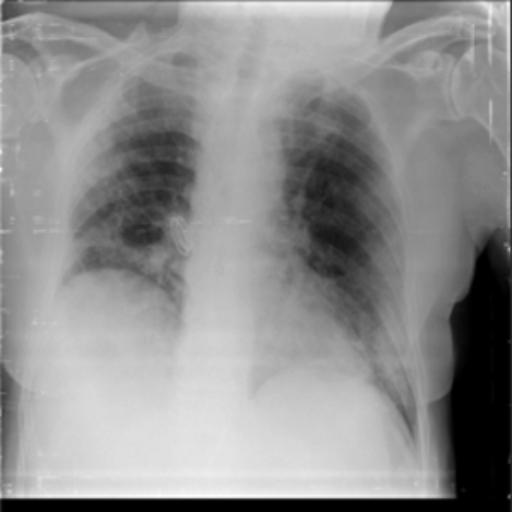

The dataset chosen in this paper is an open-source dataset, the dataset is selected from the open-source database, the database contains 150 lung X-ray images and their corresponding 150 masks, and we select four of them for presentation, the results are shown as follows, the four images in the first row are the original images of the lung X-ray, and the images in the second row in the corresponding position are their corresponding masks, as shown in Fig. 1.

Figure 1. Partial data.